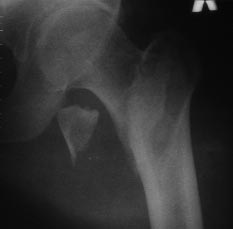

Уважаемые коллеги! На консультацию пришел больной 44-х лет (снимки 1 и 2): упал на улице 26.11.2012г., оперирован в одном из лечебных учреждений 26.11.2012. Сделали контрольные рентгенограммы и КТ. Хотели-бы обсудить варианты оперативного лечения: DHS или БИОС?

Если честно, то на первом снимке отломки "стояли" лучше, чем после "репозиции" и остеосинтеза пресловутой Г-образной пластиной-не восстановлена дуга Адамса, ну или по другому- отсутствие медиальной опоры. По этой же причине не рекомендую DHS, только штифт типа Гамма, при этом обязательно

DHS в этом случае не показан, так как перелом из чрезвертельного чудесным образом превратился в подвертельный (А 3 по классификации АО). На мой взгляд, можно рассматривать 2 варианта: